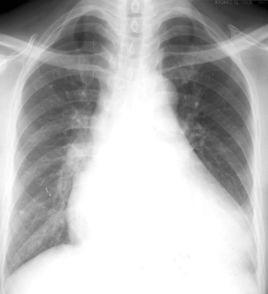

主動脈型心臟是指後前位,呈靴形,心腰凹陷,心左緣下段向左擴展,主動脈球突出,常見於高血壓病和主動脈瓣病變。